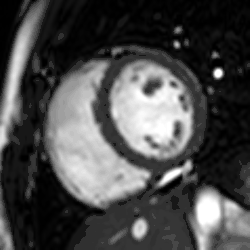

Heart function using cine imaging

Functional and structural information is acquired using bSSFP cine sequences. These are usually retrospectively-gated and have intrinsically high contrast in cardiac imaging due to the relatively high T2:T1 ratio of blood compared to myocardium. Images are typically planned sequentially to achieve the standard cardiac planes used for assessment. Turbulent flow causes dephasing and signal loss allowing valvular disease to be qualitatively appreciated. The left ventricular short axis cines are acquired from base to apex and are used for quantifying end-diastolic and end-systolic volumes, as well as myocardial mass. Tagging sequences excite a grid pattern that deforms with cardiac contraction allowing strain to be assessed.

Enlarged right ventricle with poor function in a patient with repaired tetralogy of Fallot by CMR